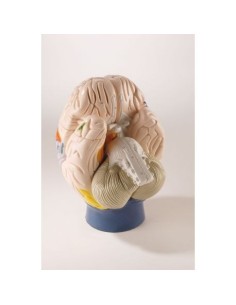

Des modèles anatomiques détaillés pour tous les besoins

Du crâne en 22 parties à verrouillage magnétique aux modèles de colonne vertébrale, des modèles d'articulation aux modèles de cœur, chaque pièce de notre collection est conçue pour une immersion totale dans l'étude de l'anatomie humaine. Nos modèles, réalisés à partir de scans d'os réels, garantissent une expérience tactile authentique et une fidélité de poids presque identique aux originaux.

Indispensables aux étudiants comme aux professionnels, nos modèles anatomiques sont des outils pédagogiques qui permettent d'observer les structures anatomiques avec précision, en évitant les dissections ou les études invasives. Ils sont également utiles pour expliquer les pathologies aux patients, ce qui rend la communication plus efficace et permet de gagner un temps précieux.